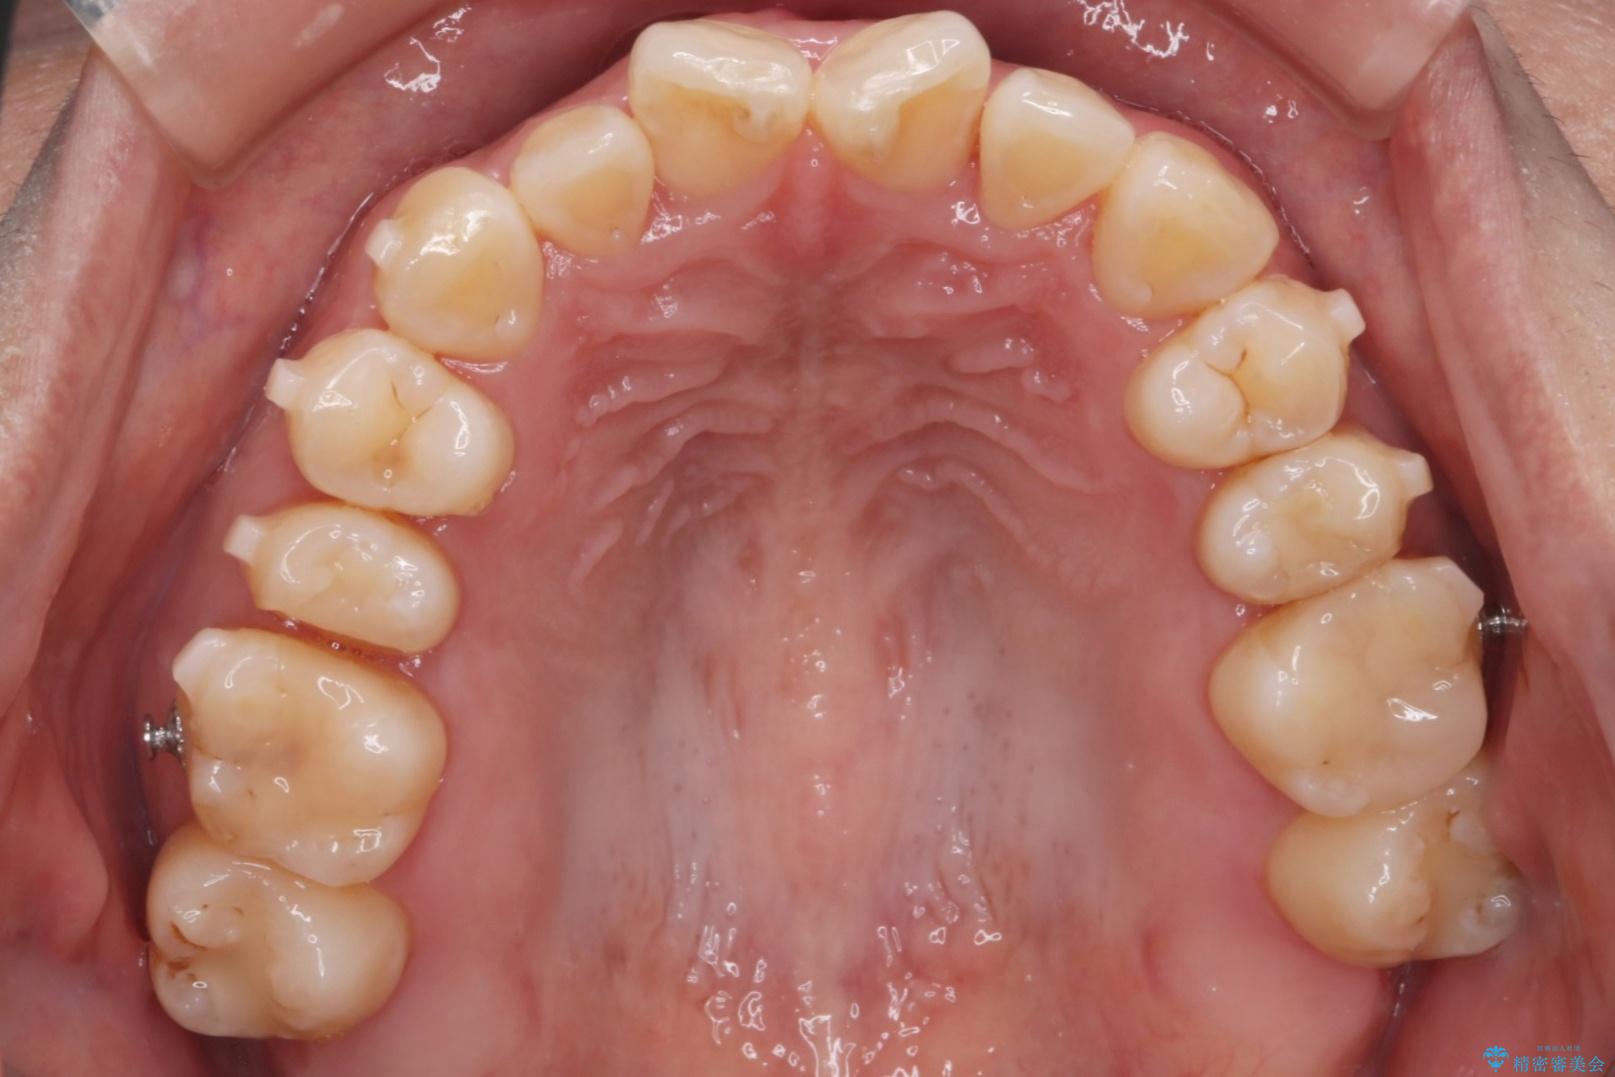

上の前歯のねじれが気になるとご来院された患者様です。

前歯の捻れとがたつきを改善するために、IPR(歯と歯の間を削る処置)と歯列拡大をすることで歯並びを整えていく治療計画を立てました。